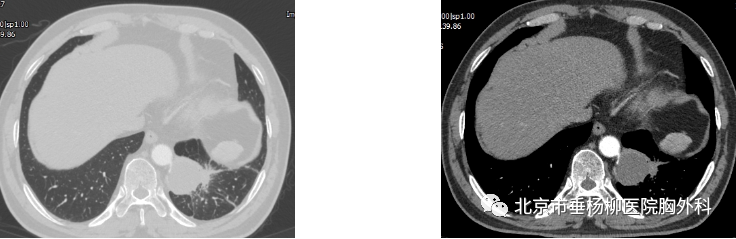

患者男性,60岁,主因“发现左肺下叶占位1月余。以“左肺下叶占位”入院,胸部增强CT:左肺下叶脊柱旁类圆形实性结节影,直径4.5*4.2cm,边界较清晰,增强扫描未见明显强化,可见腹主动脉分支血管进入病灶内。术中叶裂分化不全,左肺下叶与膈肌及纵膈胸膜粘连明显,遂行胸腔镜下左肺下叶切除术,手术历时4小时,完整切除肿物,术后病理回示:叶内型肺隔离症。术后患者恢复良好,术后5天拔出胸腔引流管,术后7天出院。

术前胸部CT(肺窗) 纵膈窗